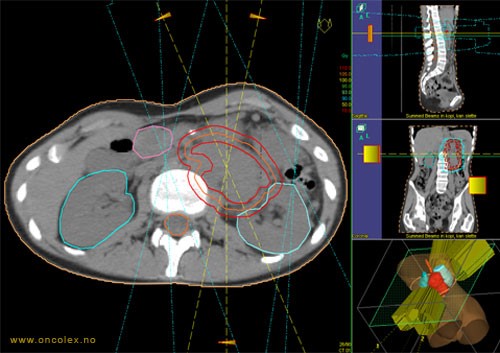

All strålebehandling er individuelt tilpasset. For at behandlingen skal kunne planlegges og gjennomføres, kreves godt tverrfaglig samarbeid av et fagteam bestående av leger, medisinske fysikere og stråleterapeuter. Legene vurderer sykdomsbildet og avgjør hvilket område som skal behandles samt hvor høy stråledose som skal gis. Antall behandlinger (fraksjoner) varierer avhengig av svulstens type, størrelse, lokalisasjon og hensikten med behandlingen. Stråleterapeuter og medisinske fysikere planlegger og kvalitetssikrer behandlingen.